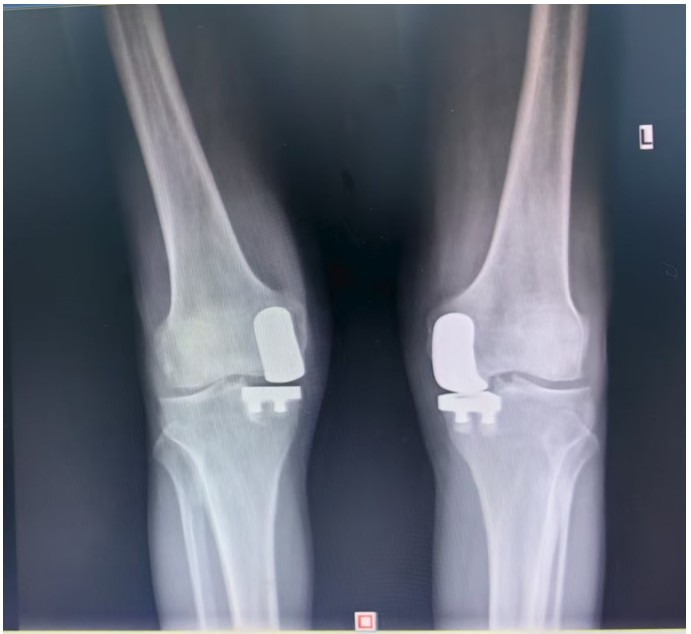

通訊員王珂報(bào)道:近日,一位來(lái)自江西的大爺跨越六百公里,專程來(lái)到衡陽(yáng)市中心醫(yī)院關(guān)節(jié)外科求診。羅湘平主任醫(yī)師、彭健副主任醫(yī)師團(tuán)隊(duì)熱情地接待了患者,并成功為其實(shí)施了“雙側(cè)人工膝關(guān)節(jié)單髁置換術(shù)(UKA)”。術(shù)后膝關(guān)節(jié)功能顯著改善,第二天便可下地活動(dòng),雙側(cè)膝關(guān)節(jié)活動(dòng)度輕松達(dá)到90°,對(duì)手術(shù)效果非常滿意,已于9月10日順利出院。

據(jù)了解,患者1年前無(wú)明顯誘因出現(xiàn)雙膝關(guān)節(jié)疼痛,以右側(cè)膝關(guān)節(jié)為主,近5個(gè)月來(lái)雙膝關(guān)節(jié)疼痛明顯加重,不但日常行走困難,生活質(zhì)量更是受到極大影響。經(jīng)多家醫(yī)院治療效果均不理想,了解到衡陽(yáng)市中心醫(yī)院關(guān)節(jié)外科在關(guān)節(jié)置換領(lǐng)域擁有豐富的臨床經(jīng)驗(yàn)和良好的患者口碑,毅然決定赴衡求醫(yī)。醫(yī)生發(fā)現(xiàn)患者雙膝關(guān)節(jié)已有內(nèi)翻畸形,關(guān)節(jié)內(nèi)側(cè)骨性膨大,X線提示雙膝退行性病變,雙膝內(nèi)側(cè)間隙明顯狹窄,手術(shù)為最佳治療方式。為了達(dá)到根治目的,羅湘平主任醫(yī)師、彭健副主任醫(yī)師為患者進(jìn)行了詳細(xì)查體及綜合評(píng)估,術(shù)前組織開(kāi)展多學(xué)科討論(MDT)。考慮到易叔叔的膝關(guān)節(jié)骨關(guān)節(jié)炎僅局限于內(nèi)側(cè),外側(cè)間室軟骨良好,若采用全膝關(guān)節(jié)置換術(shù)會(huì)將失去正常關(guān)節(jié)間室的軟骨與韌帶,創(chuàng)傷較大,便為其制定了右膝關(guān)節(jié)單髁置換手術(shù)治療方案。在充分完善術(shù)前準(zhǔn)備后,羅湘平主任、彭健副主任醫(yī)師團(tuán)隊(duì)為患者實(shí)施了右側(cè)膝關(guān)節(jié)單髁置換術(shù)。手術(shù)過(guò)程順利,團(tuán)隊(duì)?wèi)?yīng)用微創(chuàng)術(shù)式(MIS)及“精準(zhǔn)間隙平衡技術(shù)”,最大程度減少了手術(shù)創(chuàng)傷,為術(shù)后快速康復(fù)奠定了堅(jiān)實(shí)基礎(chǔ),術(shù)后第二天即可借助助行器下地活動(dòng)。6天后團(tuán)隊(duì)順利為患者實(shí)施了左側(cè)膝關(guān)節(jié)單髁置換手術(shù)。目前,易叔叔在關(guān)節(jié)外科醫(yī)護(hù)團(tuán)隊(duì)的精心指導(dǎo)和康復(fù)治療下,恢復(fù)情況良好,雙側(cè)膝關(guān)節(jié)活動(dòng)度輕松達(dá)到90°,膝關(guān)節(jié)功能顯著改善,能夠獨(dú)立下地行走,對(duì)手術(shù)效果非常滿意,已于9月10日順利出院。